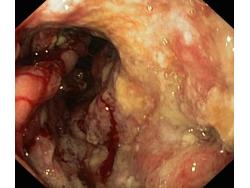

Obrazy endoskopowe

Krwawienie

Nowotwory przewodu pokarmowego